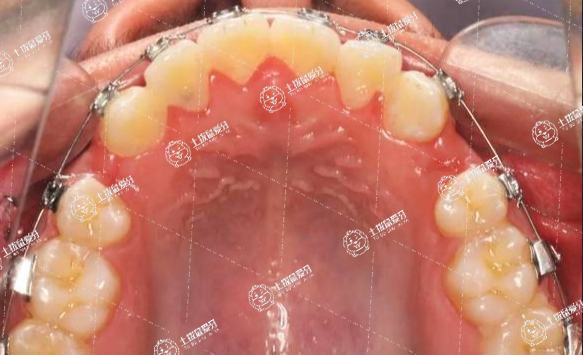

牙齒矯正要不要拔牙?這個問題是很多牙友問到我們的一個問題,他們對于拔牙這個問題都是比較重視的,有些人不想把好好的牙齒拔掉,也有些人擔心拔牙之后會有什么傷害等等,有著各種擔憂,今天就給大家解析下矯正牙齒到底需不需要拔牙吧。

1.牙列擁擠:牙槽骨小導致牙齒擁擠,無法容納現(xiàn)有的牙齒數(shù)量。

2.齙牙:要拔牙獲得空余牙間隙,才能把前牙向內(nèi)收,把后牙向前移動,把牙間隙關(guān)閉。

3.咬合關(guān)系的需要:上下牙咬合不對稱,需拔牙獲得牙間隙,才能調(diào)整后牙咬合關(guān)系。

矯正沒有絕對的拔牙和不拔牙之分,具體還是看要個人的頜骨量與牙量的關(guān)系,以及想要達到什么樣的效果為準。